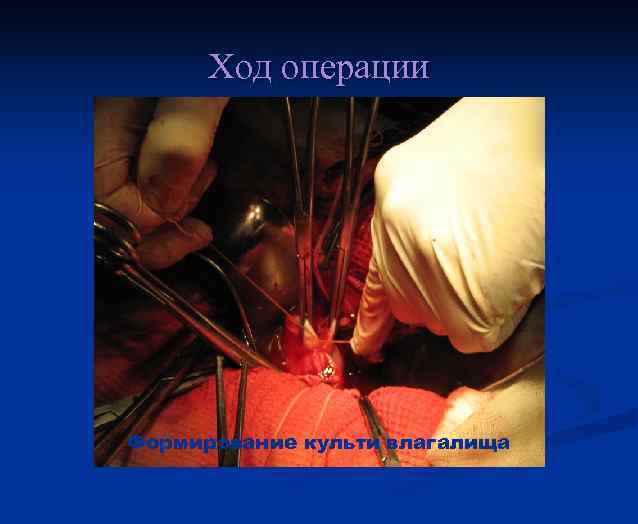

Ход операции Формирование культи влагалища